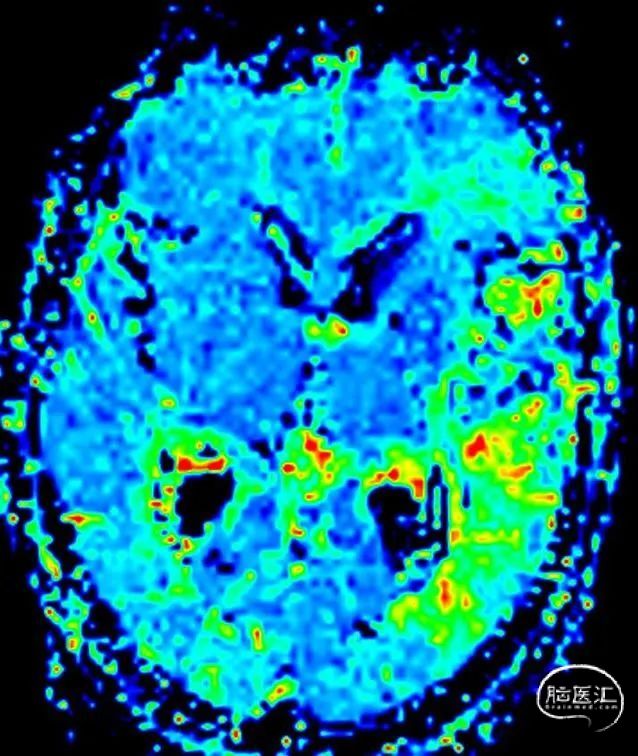

MR灌注

MTT

TTP

CBF

CBV